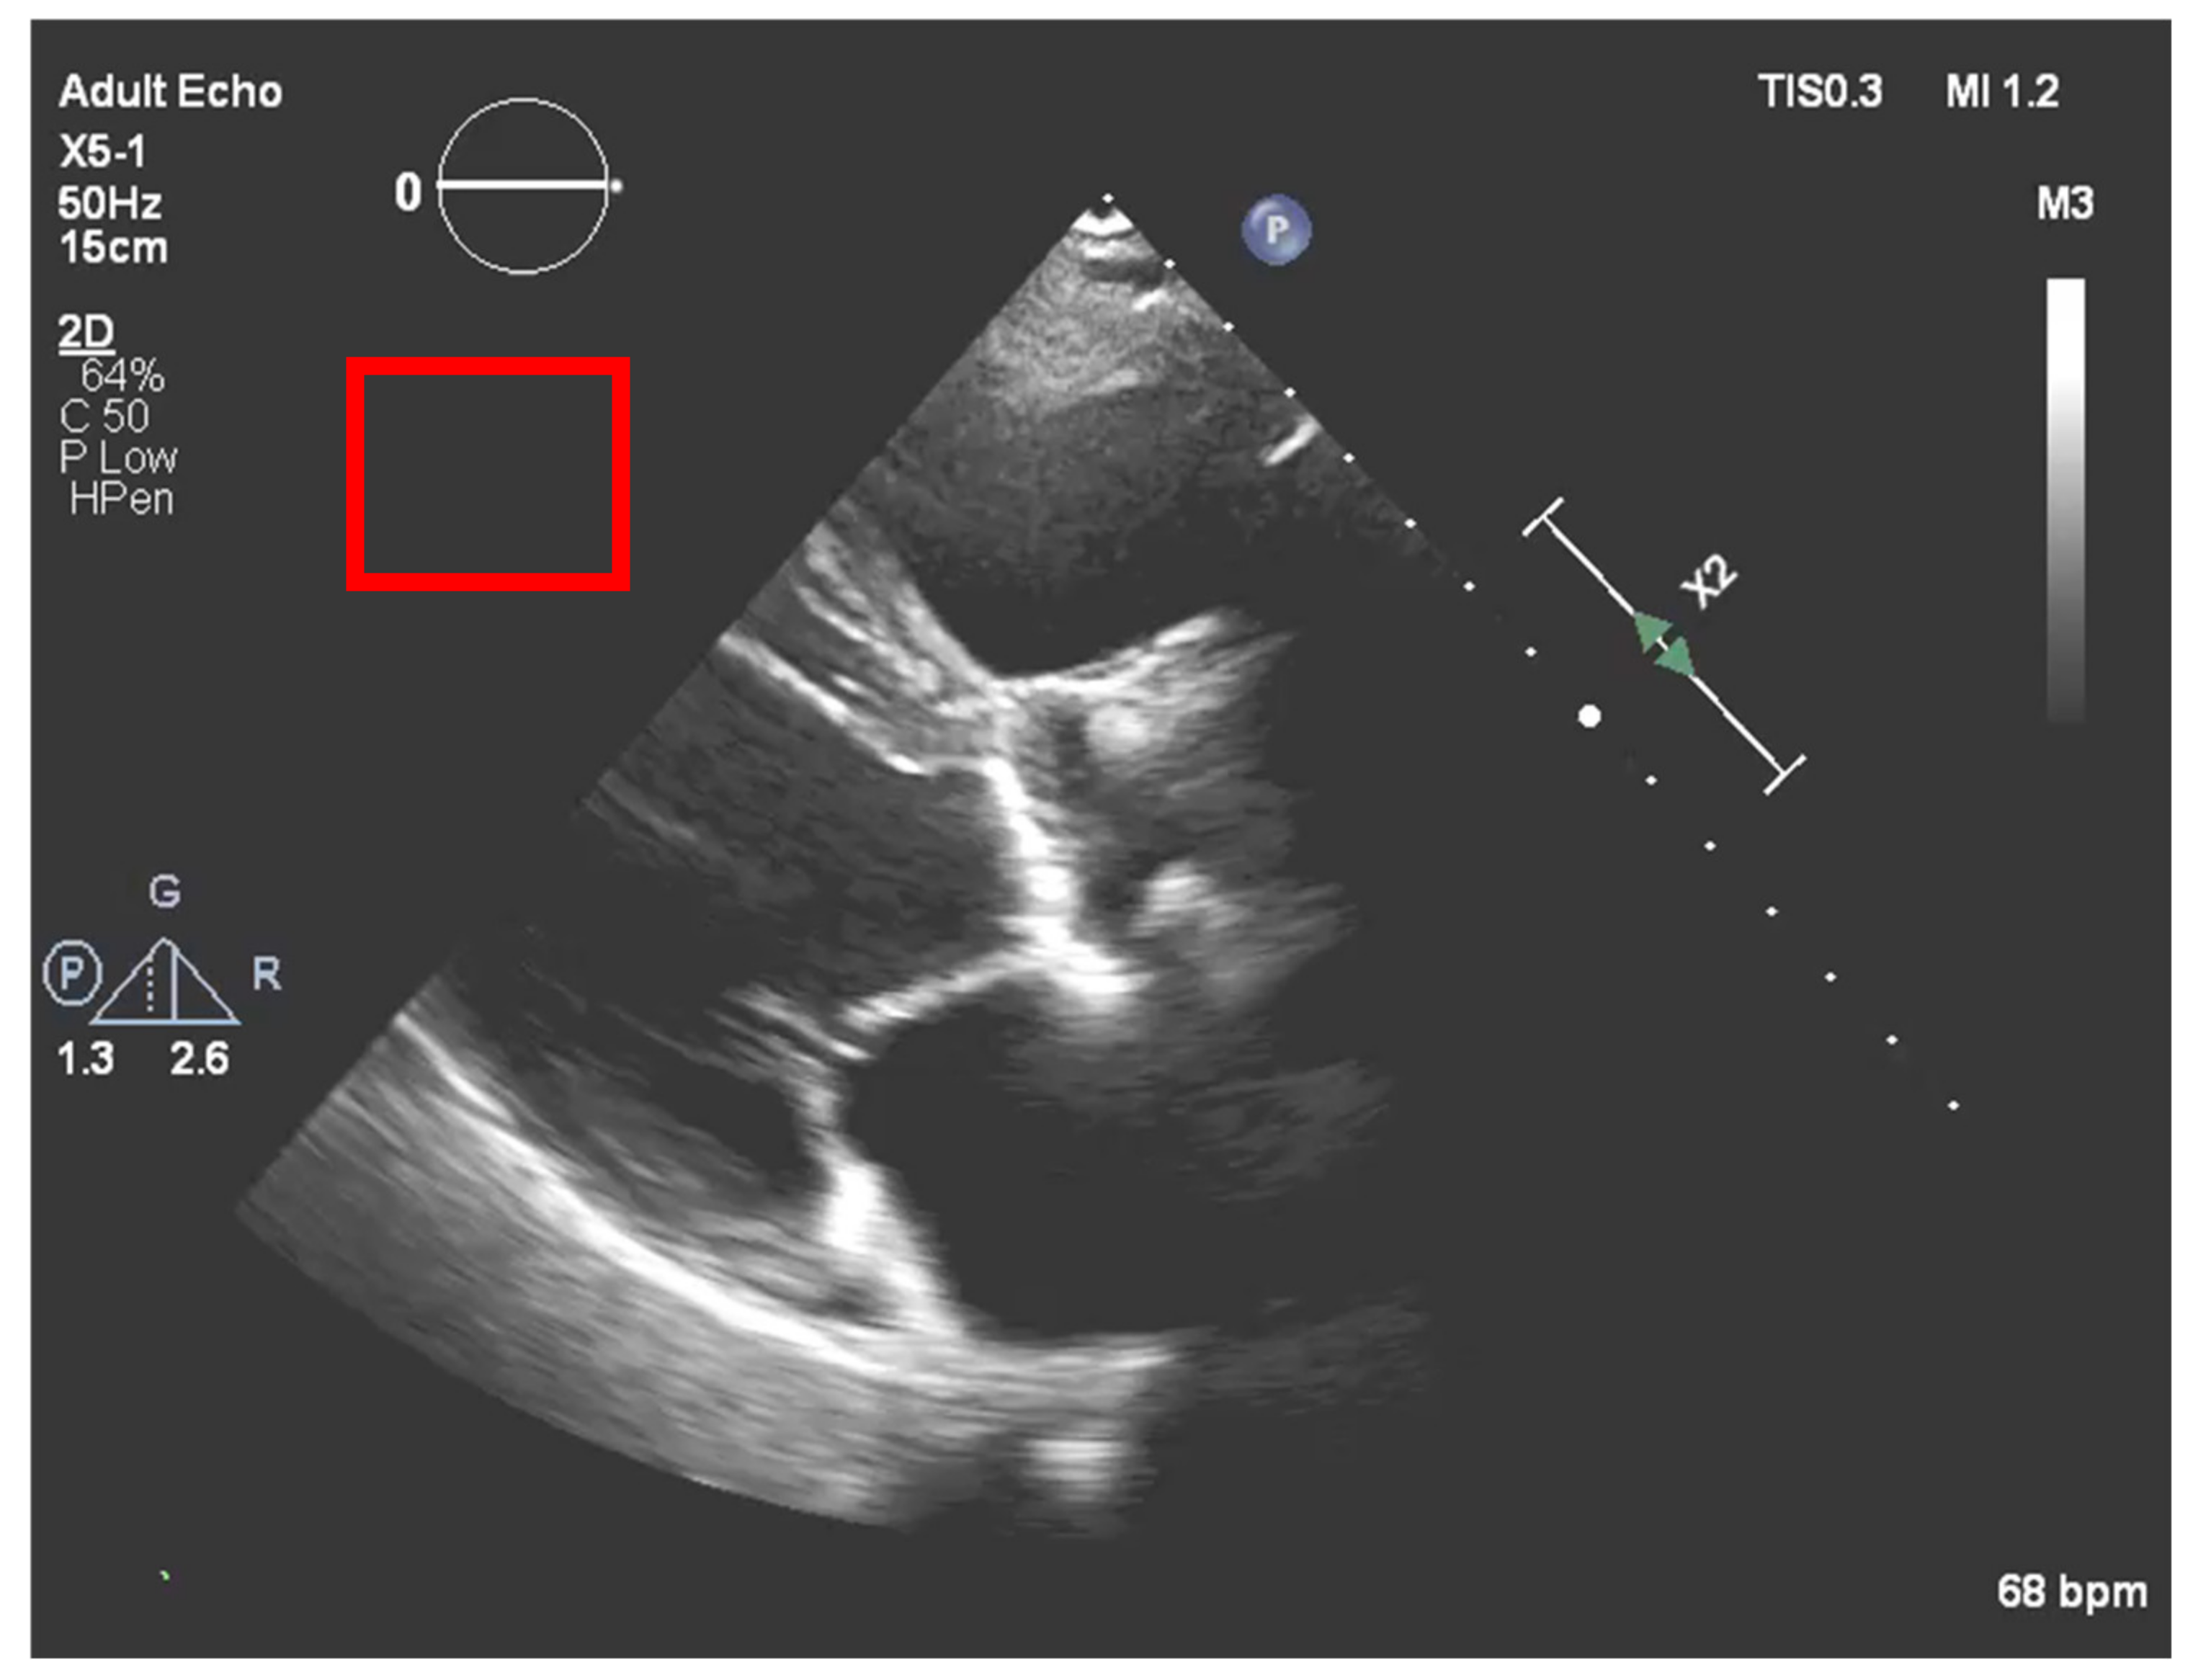

After the echocardiography raw data acquisition, gains are added to the image in a post-processing procedure. In our process, it is necessary to compensate for the new brightness that the image acquires by such a process. To accomplish this, a region outside the ultrasound sector was selected that would act as a normalization boundary of “dark” regions, as represented in Figure 7.

In this section, the system asks the user if the echocardiography selected has post-processing gains. If the image was subjected to such a processing stage, it is crucial to compensate them to get the real acquisition values and to ensure a more precise result. To do this, the user needs to select a region out of the sector, as represented in Figure 7.

This process will exclude the new brightness and treatment given on post-processing, achieving the original image collected by the specialist.

Figure 7. Normalization region of interest (red square) to compensate the post image processing.